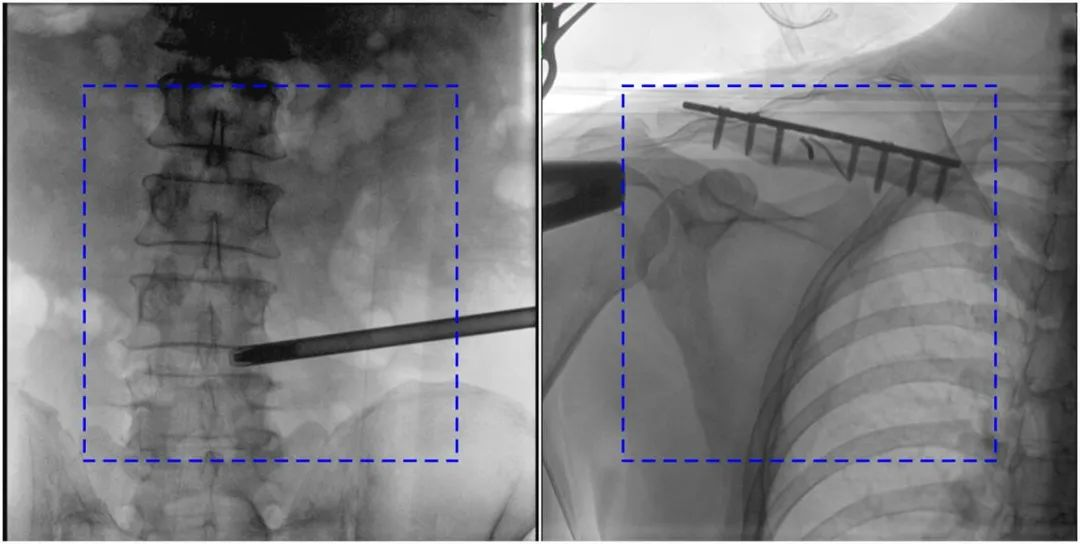

與傳統(tǒng)的21CM×21CM成像尺寸相比,普愛醫(yī)療大平板一體式C形臂具有30CM×30CM更大成像尺寸,能夠一次成像5.5節(jié)椎體,呈現更全面的影像信息,即便是手術經驗不豐富的年輕醫(yī)生也能通過圖像迅速判斷椎體節(jié)段、定位手術部位,避免因為視野不足而造成的多次定位、反復曝光,提高效率的同時避免過量攝入輻射。

普愛醫(yī)療大平板一體式C形臂圖像與傳統(tǒng)圖像對比(藍色虛線內為傳統(tǒng)21CM×21CM平板的成像區(qū)域)